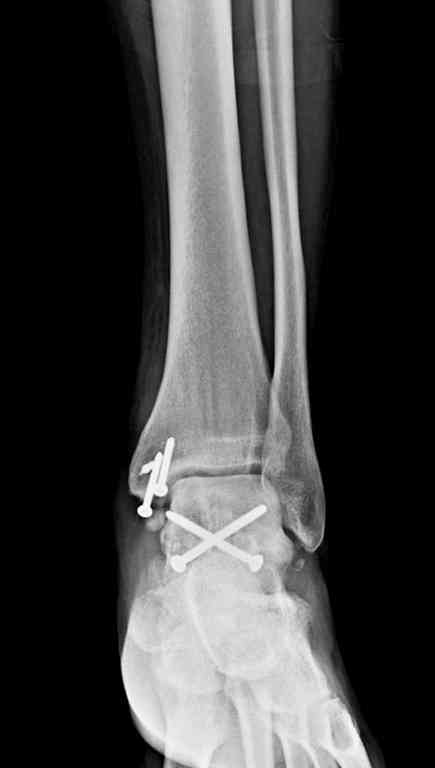

Переломовывих тарана с повреждением медиальной стороны. Через 4 часа после поступления проведена репозиция и фиксация тарана после Irrigation&Debridment. Частичное несращение медиальной лодыжки не беспокоит, вернулся к активному образу жизни. Полная нагрузка разрешена через 11 недель. Финальные снимки через 11 месяцев.

Из-за многооскольчатости дистальной части малоберцовой, где невозможно было провести фиксацию шурупами, перелом зафиксирован подпирающей пластиной, которая должна служить дополнением отсутствующей дистальной части малоберцовой (lateral cortex substitute).

Для стабильности два шурупа на синдесмоз.

Медиальную рану с приближенными краями продолжаем вакуумировать (KCI). Наружный фиксатор оставлен на пару недель, надеюсь, небольшая рана будет гранулировать и закроется без кожной пластики. Фиксация медиальной ложыжки не планируется.